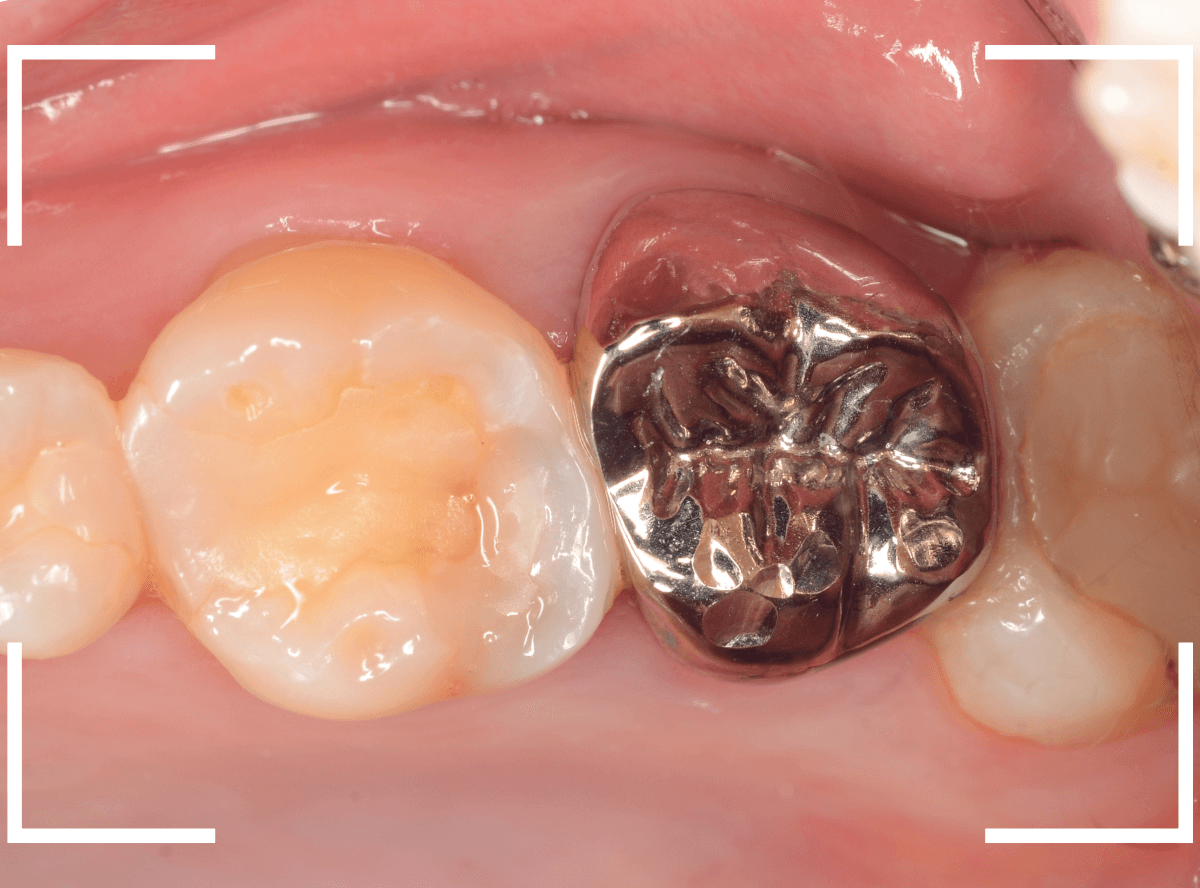

Case.20 メタル・インレーとメタル・クラウンをジルコニアにやり替え

「下の奥歯の銀歯を白くしたい」というご希望の患者さんです。

メタル・インレーとメタル・クラウンが入っていますね。

検査の結果、再製に問題なさそうでしたので、治療を進める事になりました。

まずは、奥のメタル・クラウンを外します。